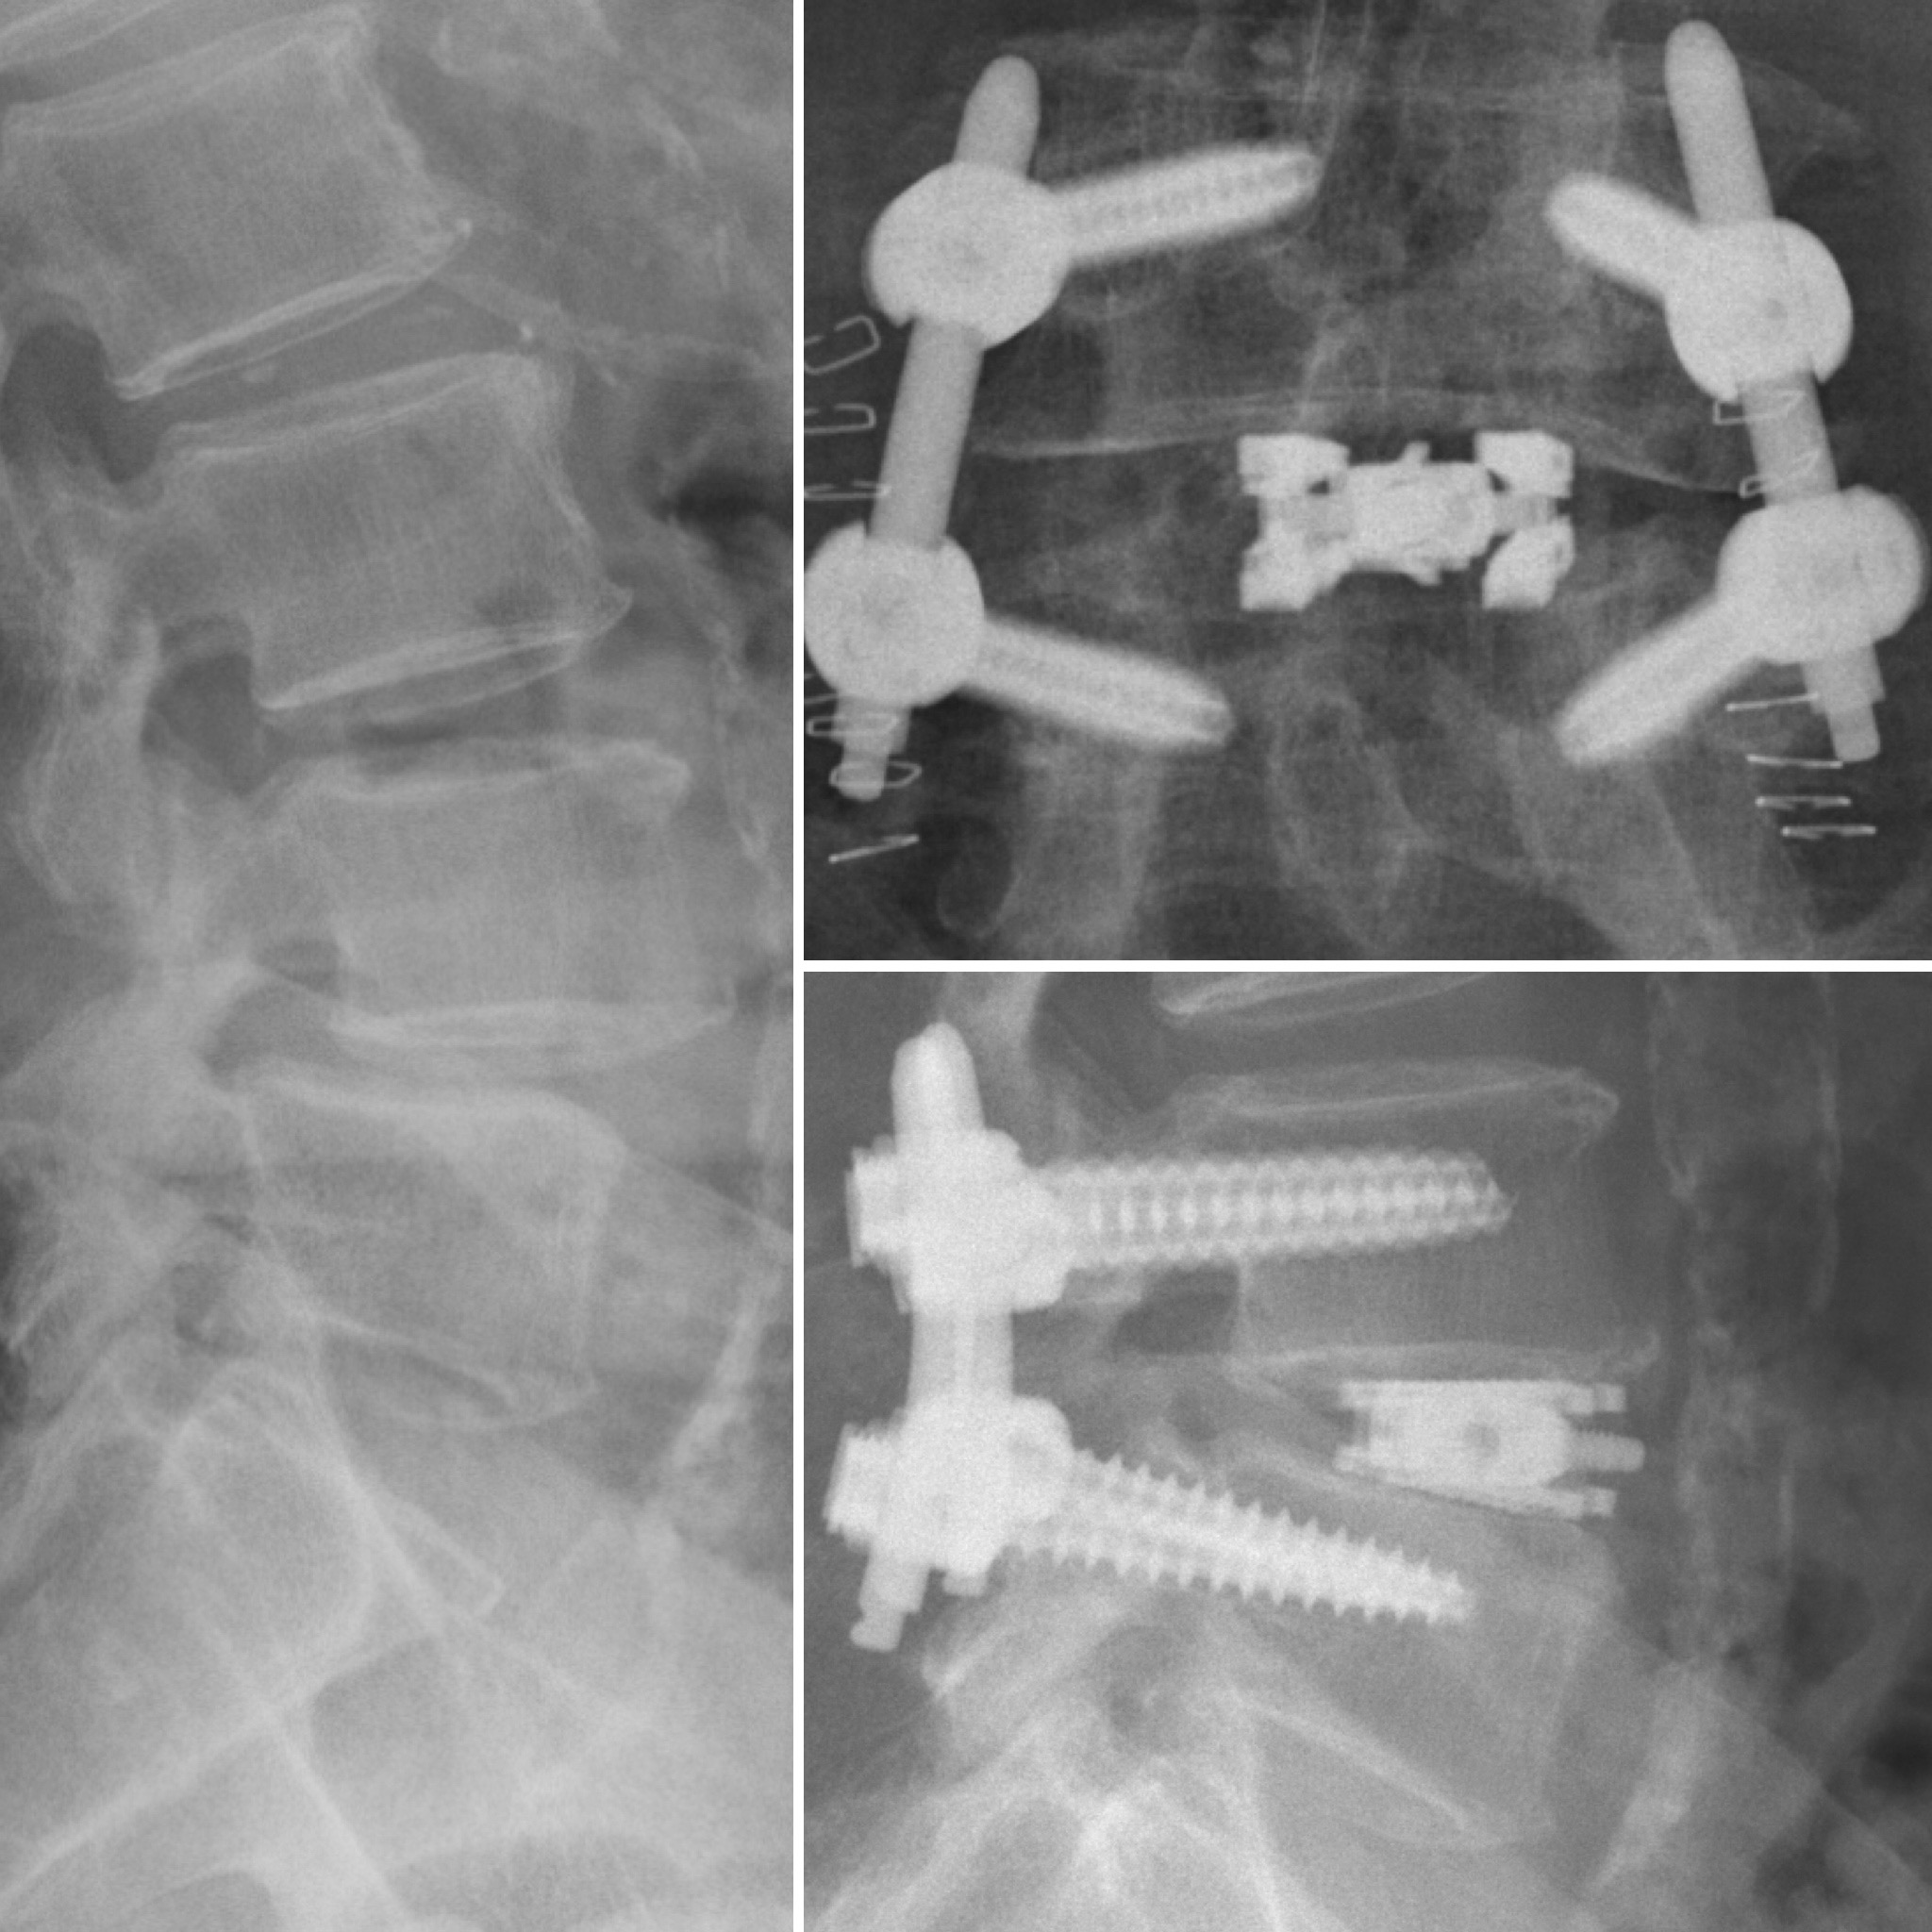

dualX®Slim transforms the fusion environment from insertion to spinal restoration by delivering a powerful dual-expanding implant through a minimally-invasive or endoscopic approaches. dualX®Slim has one of the smallest insertion profiles in the market while still expanding in both horizontal and vertical directions to provide an ALIF-sized final geometry with higher degrees of lordosis (8°, 12°, 15°, 18°*) through the patented trueLordosis™ technology.

Lateral expansion establishes stable footprint Large, center bone graft chamber for post-expansion grafting

20 mm Fully Expanded Width

Powerful vertical expansion restores disc height for decompression

Vertical expansion assists in direct and indirect decompression Multiple lordotic angles restore sagittal balance

8°, 12°, 15°, 18°*

Mechanically, it's a great construct. The other major advantage dualX®Slim implant has is the post expansion fill. The expansion—which is the footprint—is biomechanically stable. I have no doubt that it's a more stable construct compared to a much smaller device that is not point loading or edge loading the end plates. And then the fact that you can really put quite a bit of graft in the disk space that you know surrounds the entire cage is—from a technical standpoint—really a major advantage in my opinion.

Over the last three-to-four years, I've really transitioned the vast majority of my interbody cases to an MIS TLIF approach using dualX® implants, and I've been very pleased with the outcomes—both radiographically and clinically.